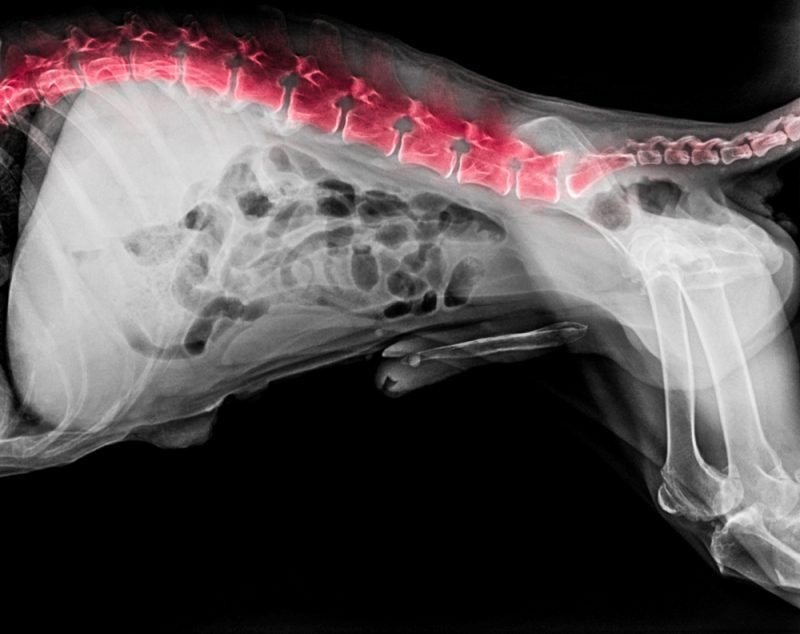

Dog Intervertebral Disc Disease Veterinary . canine intervertebral disk disease (ivdd) and chronic spinal cord compression were first described in the late 1800s. evidence of intervertebral disk degeneration (ivdd) is extremely common in dogs, and its prevalence increases with age. Today, ivdd is the most. nonchondrodystrophoid dogs (labrador retrievers, german shepherd dogs, etc.) usually present between 5 and 12 years of. there are two main types of disease that can afflict the intervertebral disk, causing it to press painfully against the. intervertebral disc disease, methylprednisolone sodium succinate, mri intervertebral disc disease (ivdd) is a common cause of pain. intervertebral disc disease (ivdd) is a common source of back pain in dogs, especially in older dogs but also in younger dogs of.